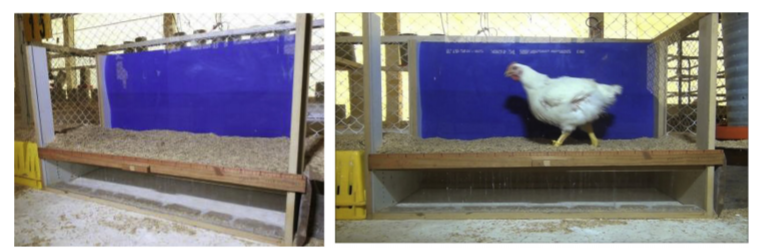

O Gait Score é uma metodologia desenvolvida para avaliar o bem-estar animal das aves em sistemas de produção. Este método vem sendo empregado para identificar e determinar a incidência de distúrbios locomotores, quando se atribui uma nota à habilidade da ave em caminhar um metro sobre uma superfície plana (Kestin et al., 1992).

Entende-se que a forma como um frango de corte caminha, por exemplo, pode apresentar um bom indicativo sobre suas condições de bem-estar. Verifica-se a capacidade de locomoção de uma ave sobre uma superfície à distância de um metro. Uma ave normal (score 0) deve andar normalmente, sem claudicações, e dar no mínimo 10 passos a essa distância. Uma ave com score 2, que apresenta muita dificuldade para caminhar, dá menos de seis passos ininterruptos na mesma distância de um metro (Kealy, 1987).

A metodologia do Gait Score é amplamente utilizada, especialmente por importadores de frangos, como forma de avaliar o bem-estar das aves. Alguns importadores estabeleceram, inclusive, que lotes com 30% ou mais de aves com Gait Score igual ou maior a 1, não apresentam aptidão para importação (Almeida Paz, 2008). Devido ao amplo uso para fins de exportação, a metodologia Gait Score se apresenta como uma boa ferramenta – de reconhecimento internacional – para avaliação do bem-estar. Contudo, o Gait Score pode ser pouco preciso quando se busca correlações entre problemas locomotores de frangos de corte e seu score (Garner et al., 2002). Isso ocorre porque o método é de natureza empírica, portanto frangos acometidos – ou não – por problemas locomotores podem apresentar a mesma atribuição de nota (score).